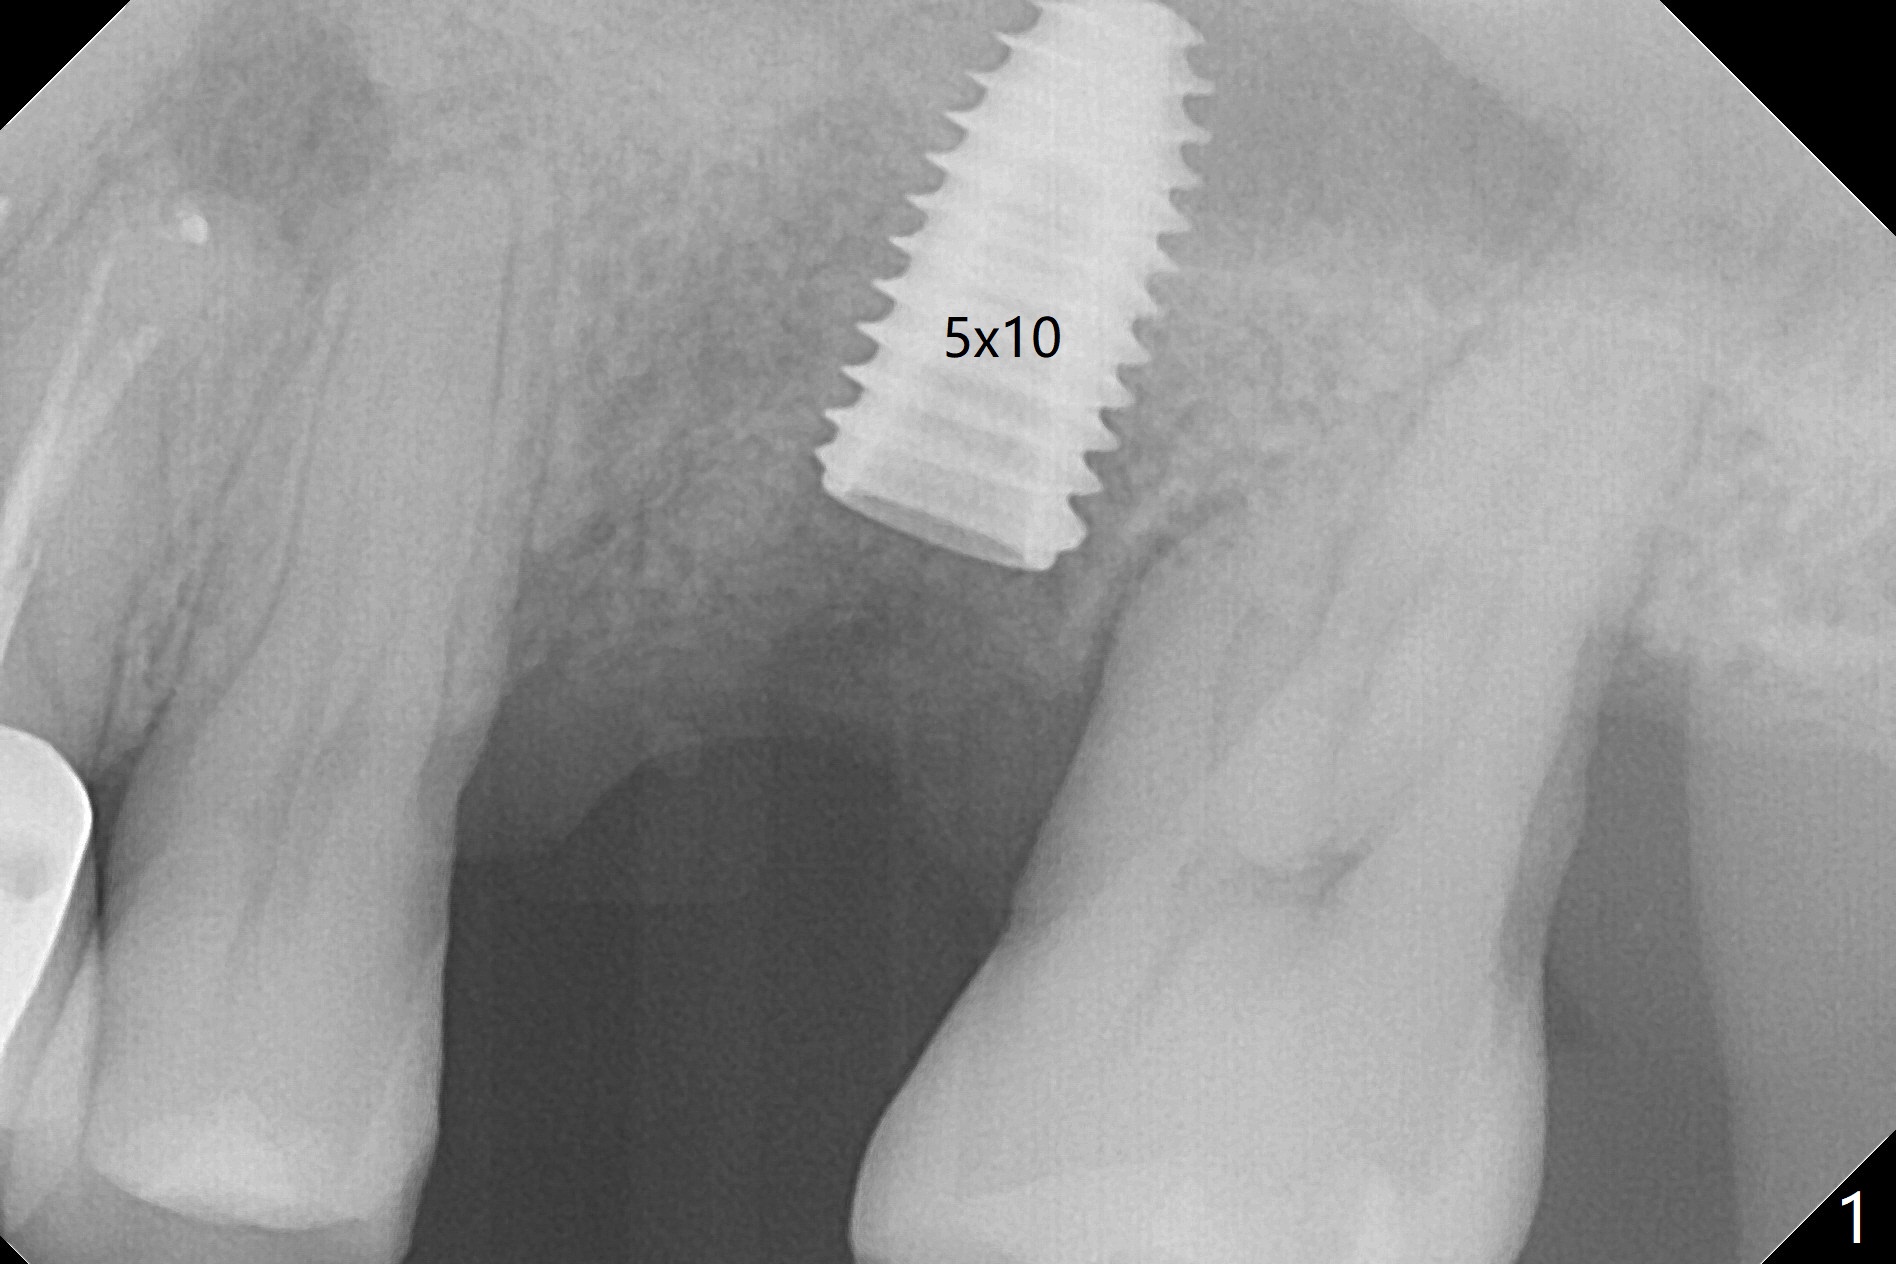

Six months post 2nd placement at #14, the 5x11 mm IBS implant is unstable. The patient smokes a cigarette a day.  After implant removal, the palatal wall of the osteotomy is intact, although low.  With removal of minimal granulation tissue, a 5x10 mm IS dummy implant is placed with stability and slightly subgingival palatal (Fig.1,2).  A 5x8.5 mm definitive implant is placed with ~ 40 Ncm and 3-4 mm subgingival palatal (Fig.3,4).  A 5.7x5.5(5) mm abutment is placed to hold periodontal dressing in place.  If the implant fails again, bone graft should be placed.  The abutment and implant are stable 4.5 months postop (Fig.5); a provisional is fabricated for progressive loading.  The provisional at #14 is narrow mesiodistally, while the tooth #15 is mesially tilted and shifted because of chronic periodontitis and 1 year 4 months of edentulism (Fig.6*).  Limited orthodontics is necessary prior to final restoration.  The 1st step is to raise the occlusion with #14 temporary reline (Fig.7 *); the tooth #15 is distalized initially with a separator, which is inefficient.  It appears that brackets and bands should be placed for distalization.  A month post banding, open coil spring is placed between #14 and 15; with occlusal composite on the opposing tooth (#19) (Fig.8), the tooth #15 is distalized instantly probably related to its periodontal condition (Fig.9 mirror view).  The tooth #15 is further distalized 2 weeks post open coil spring placement (Fig.10).  To act an anchorage, the abutment needs to be torqued with wrench (25-30 Ncm) and the provisional has to be permanently cemented.  The distalization appears to be ~ 1 mm shy 1.5 months post open coil (Fig.11).